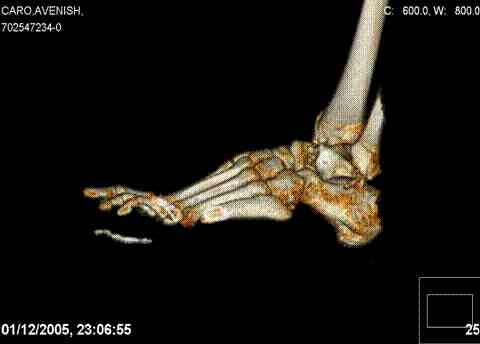

ya by popytalsya sobrat talus anatomichno,seichas pozdno operirovat iz za oteka,po etomy distrakziya apparatom budet optmalna.Posyalu vam podobyai moi sluchai.

14 years old girl

Fall from height ( 3rd floor)

Compressed fractures of L1-L2

Fx of orbital bone

Mark, судя по снимкам в день поступления произведен А.В.Ф., а остеосинтез ч-з какое время произведен?, остеосинтез произвели открытым способом?( на снимке п/о рубцы).

aparat postavlen v den postupleniya,rastaynuli, vpravili zakryto naskolko vozmoghno, a kogda otek spal sdelali otkrytoe vpravlenie.Teryat tut nechego, moghno tolko uluchshit.